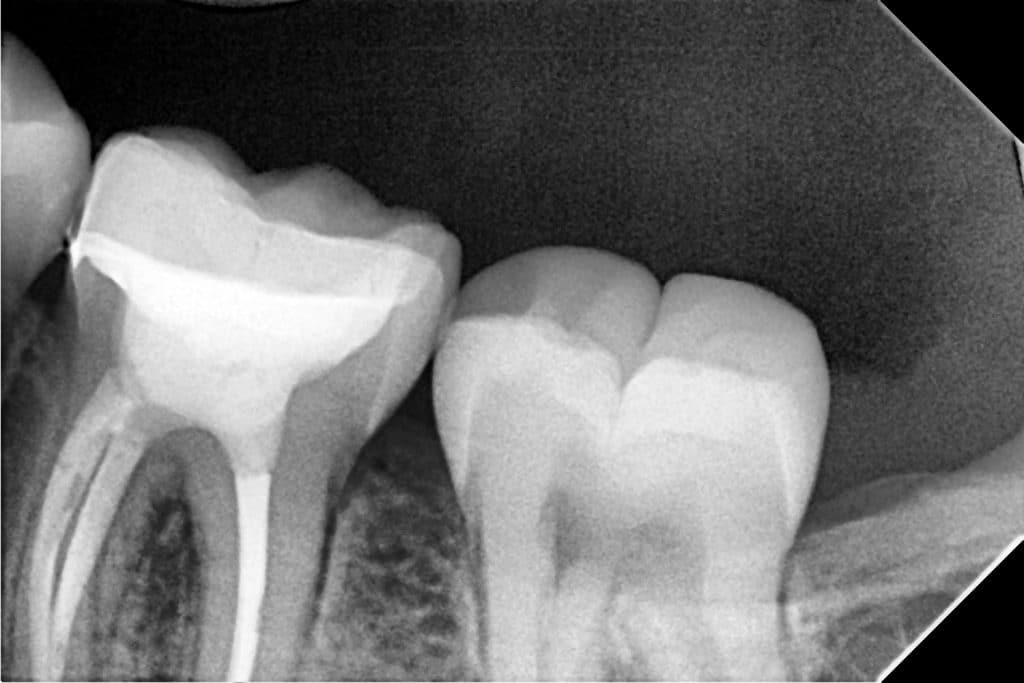

The whole buccal wall was involved and the carious lesion extended sub gingivally .

We save about half a tooth with partial coverage.